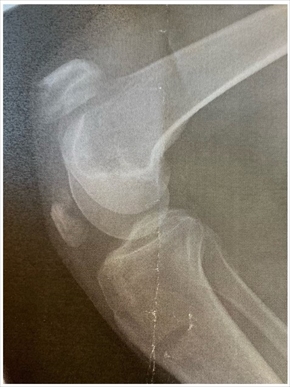

2020年8月に雨にぬれた地面に足を滑らせて転倒し、左膝蓋骨骨折の大ケガを負ったLiLiCoさん。ブログの最新エントリでは、「ズッコケてから8月13日で3年が経つ 膝の皿って折れるとは(笑)」と膝の皿が上下に割れたレントゲン写真を添えて当時を振り返っており、「わたしは3年間通院してた 骨の経過、リハビリの経過….そして昨日!! これで通院は終わり」とめでたく最後の通院日を迎えたことを伝えました。